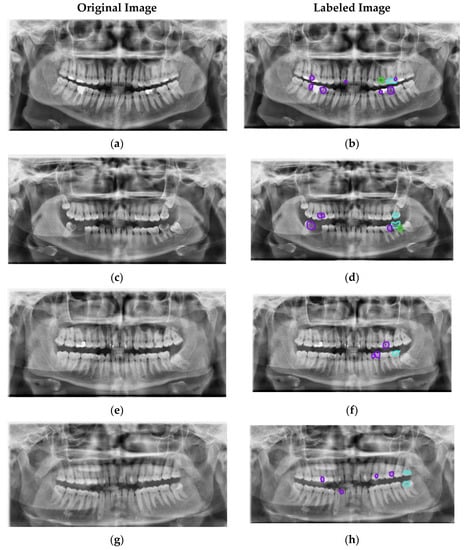

Type I (Occlusal caries).

Type II (Proximal caries).

Type III (Cervical caries).